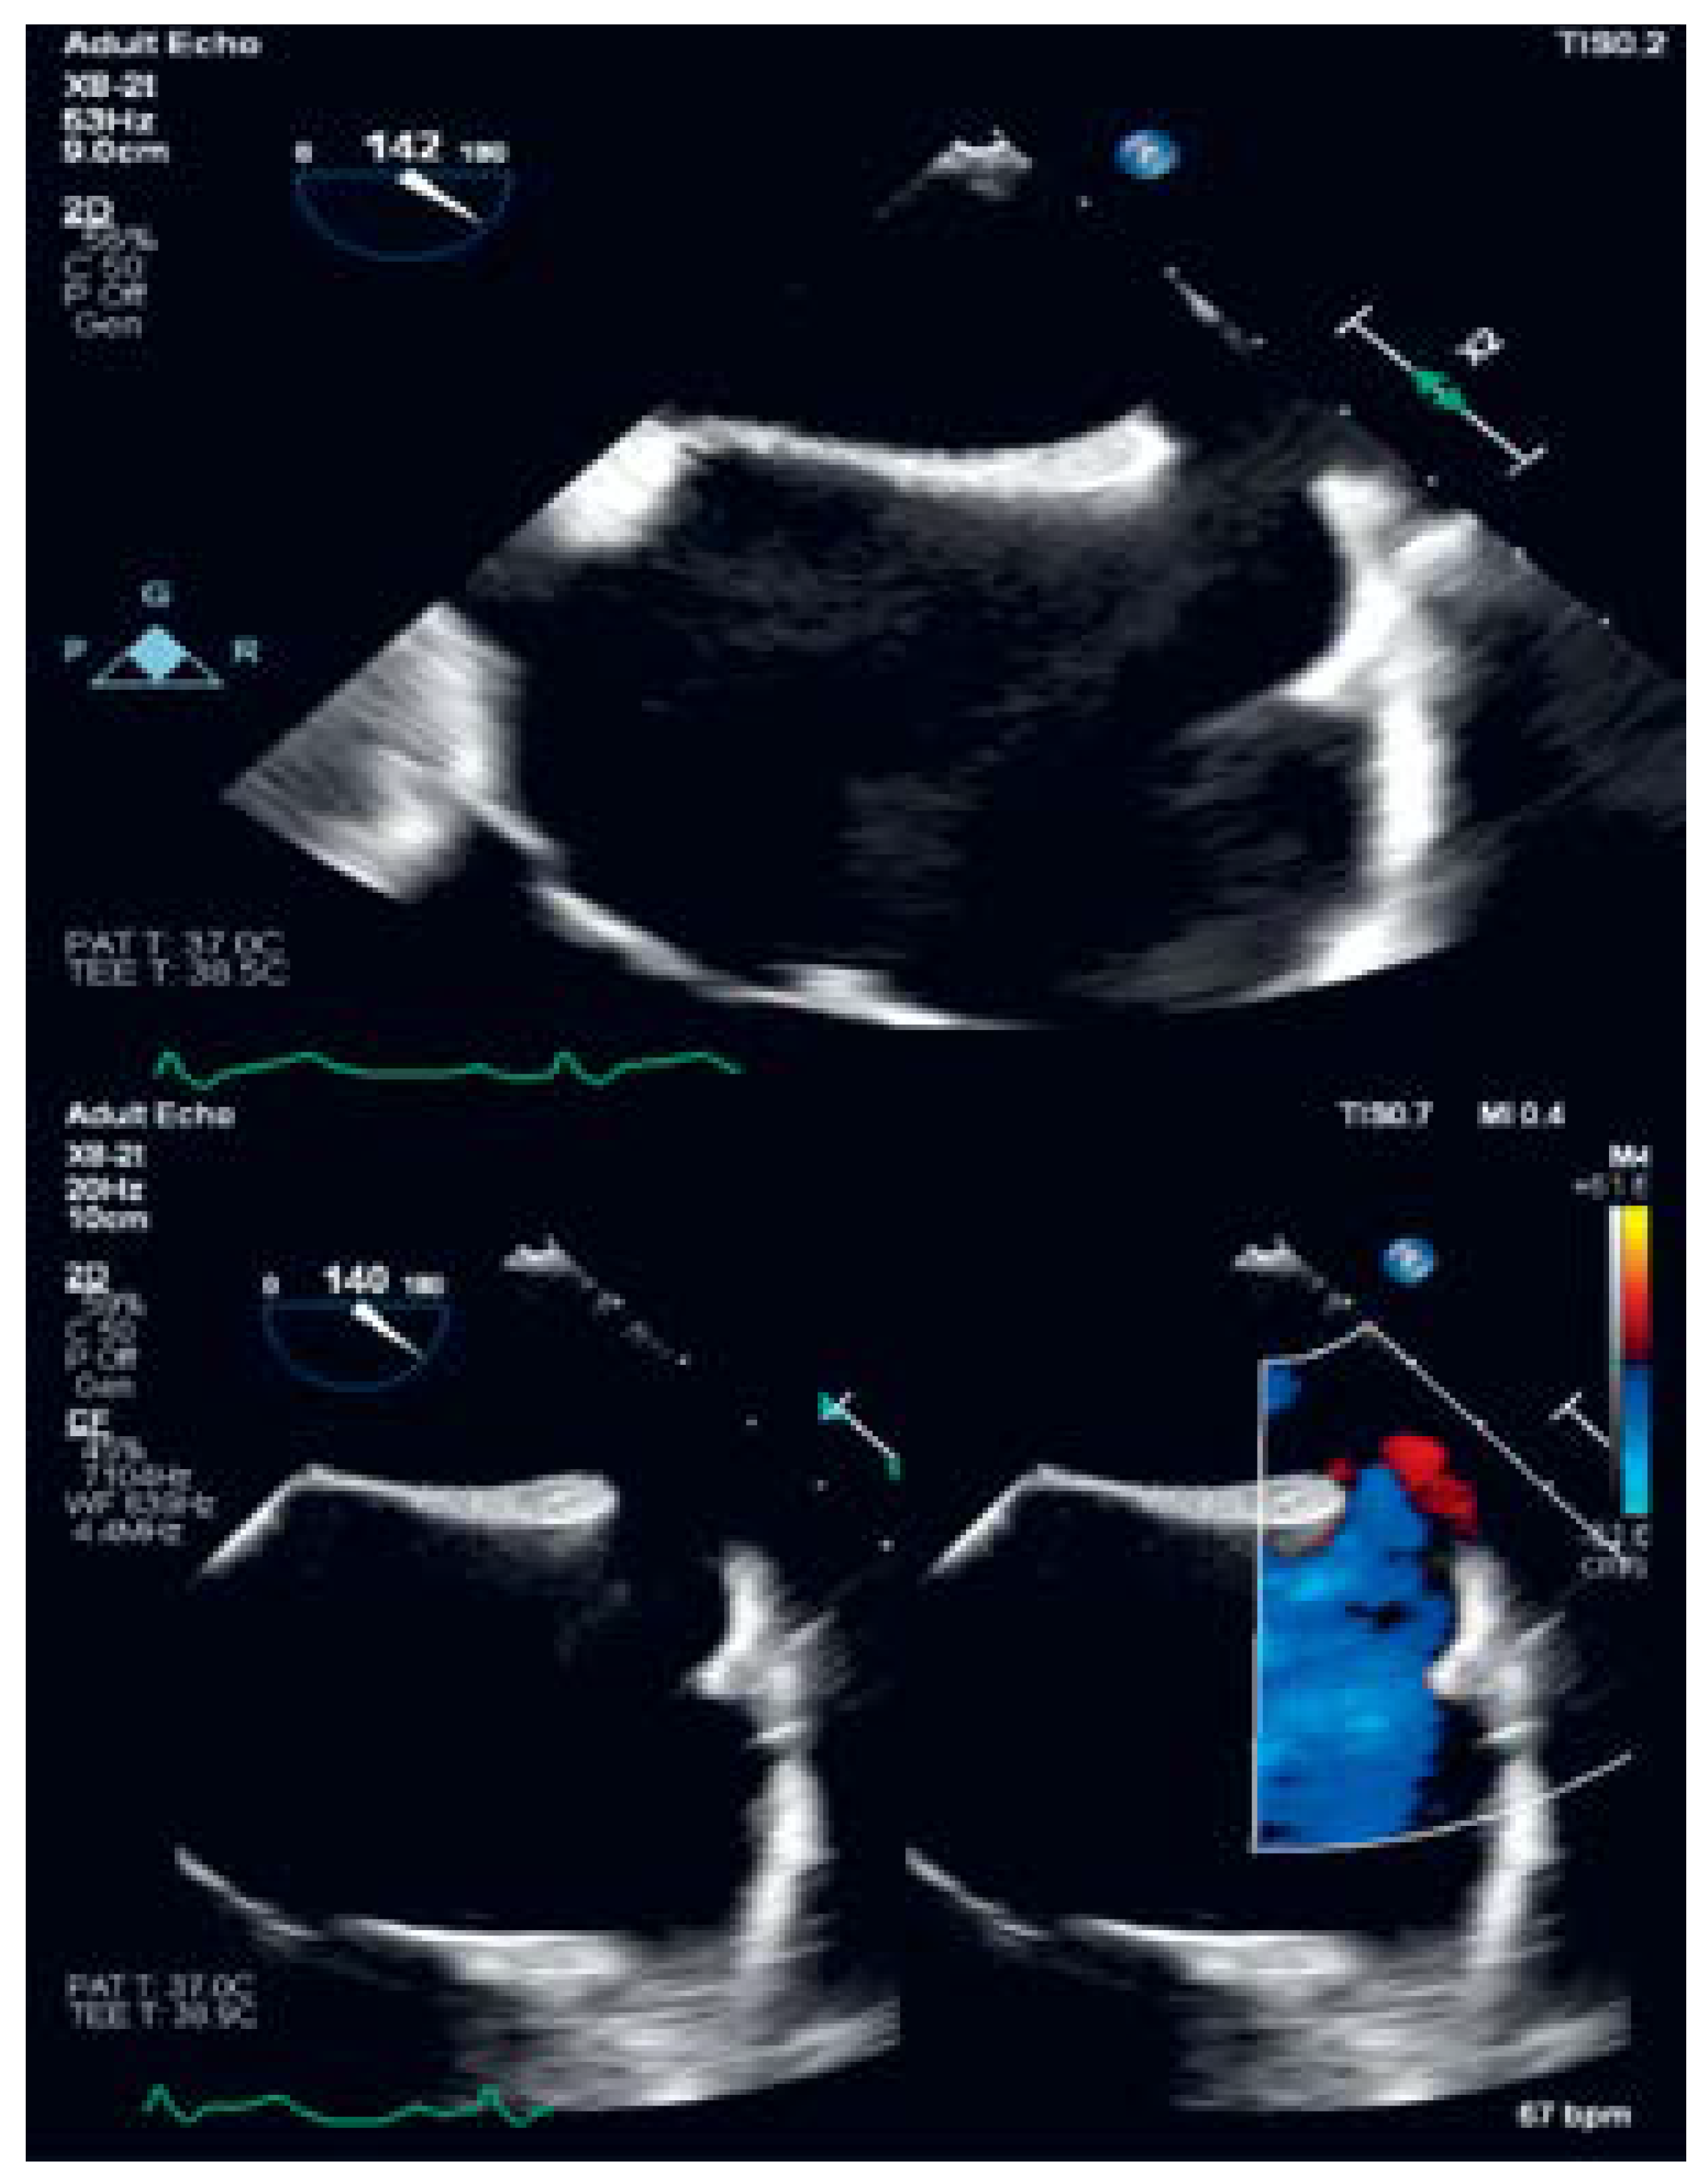

Sinus Venosus Atrial Septal Defect with Partial Anomalous Pulmonary Vein Return †

Case description